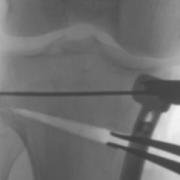

Laminar spreaders open the wedge of a high tibial osteotomy, and then the bone is held in the new position with a plate and screws until new bone fills the gap.